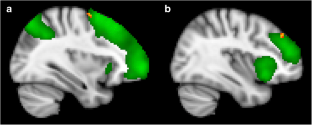

Cluster headache (CH) shows a more severe clinical picture than migraine (Mig). We tested whether brain changes can explain such difference. Multimodal MRI was acquired in attack-free patients with CH (n = 12), Mig (n = 13) and in normal controls (NC, n = 13). We used FSL for MRI data analysis and nonparametric permutation testing for voxelwise analyses (p < 0.01, corrected). CH showed lower grey matter (GM) volume, compared to Mig and NC, in frontal cortex regions (inferior frontal gyrus and frontal pole [FP], respectively) and, only compared to Mig, in lateral occipital cortex (LOC). Functional connectivity (FC) of CH was higher than Mig and NC within working memory and executive control networks and, only compared to Mig, between cerebellar and auditory language comprehension networks. In the attack-free state, the CH brain seems to be characterized by: (i) GM volume decrease, compared to both Mig and NC, in pain modulation regions (FP) and, only with respect to Mig, in a region of visual processing modulation during pain and working memory (LOC); (ii) increased FC at short range compared to both Mig and NC and at long range only with respect to Mig, in key cognitive networks, likely due to maladaptation towards more severe pain experience.

Fig. 1

Fig. 2

Fig. 3